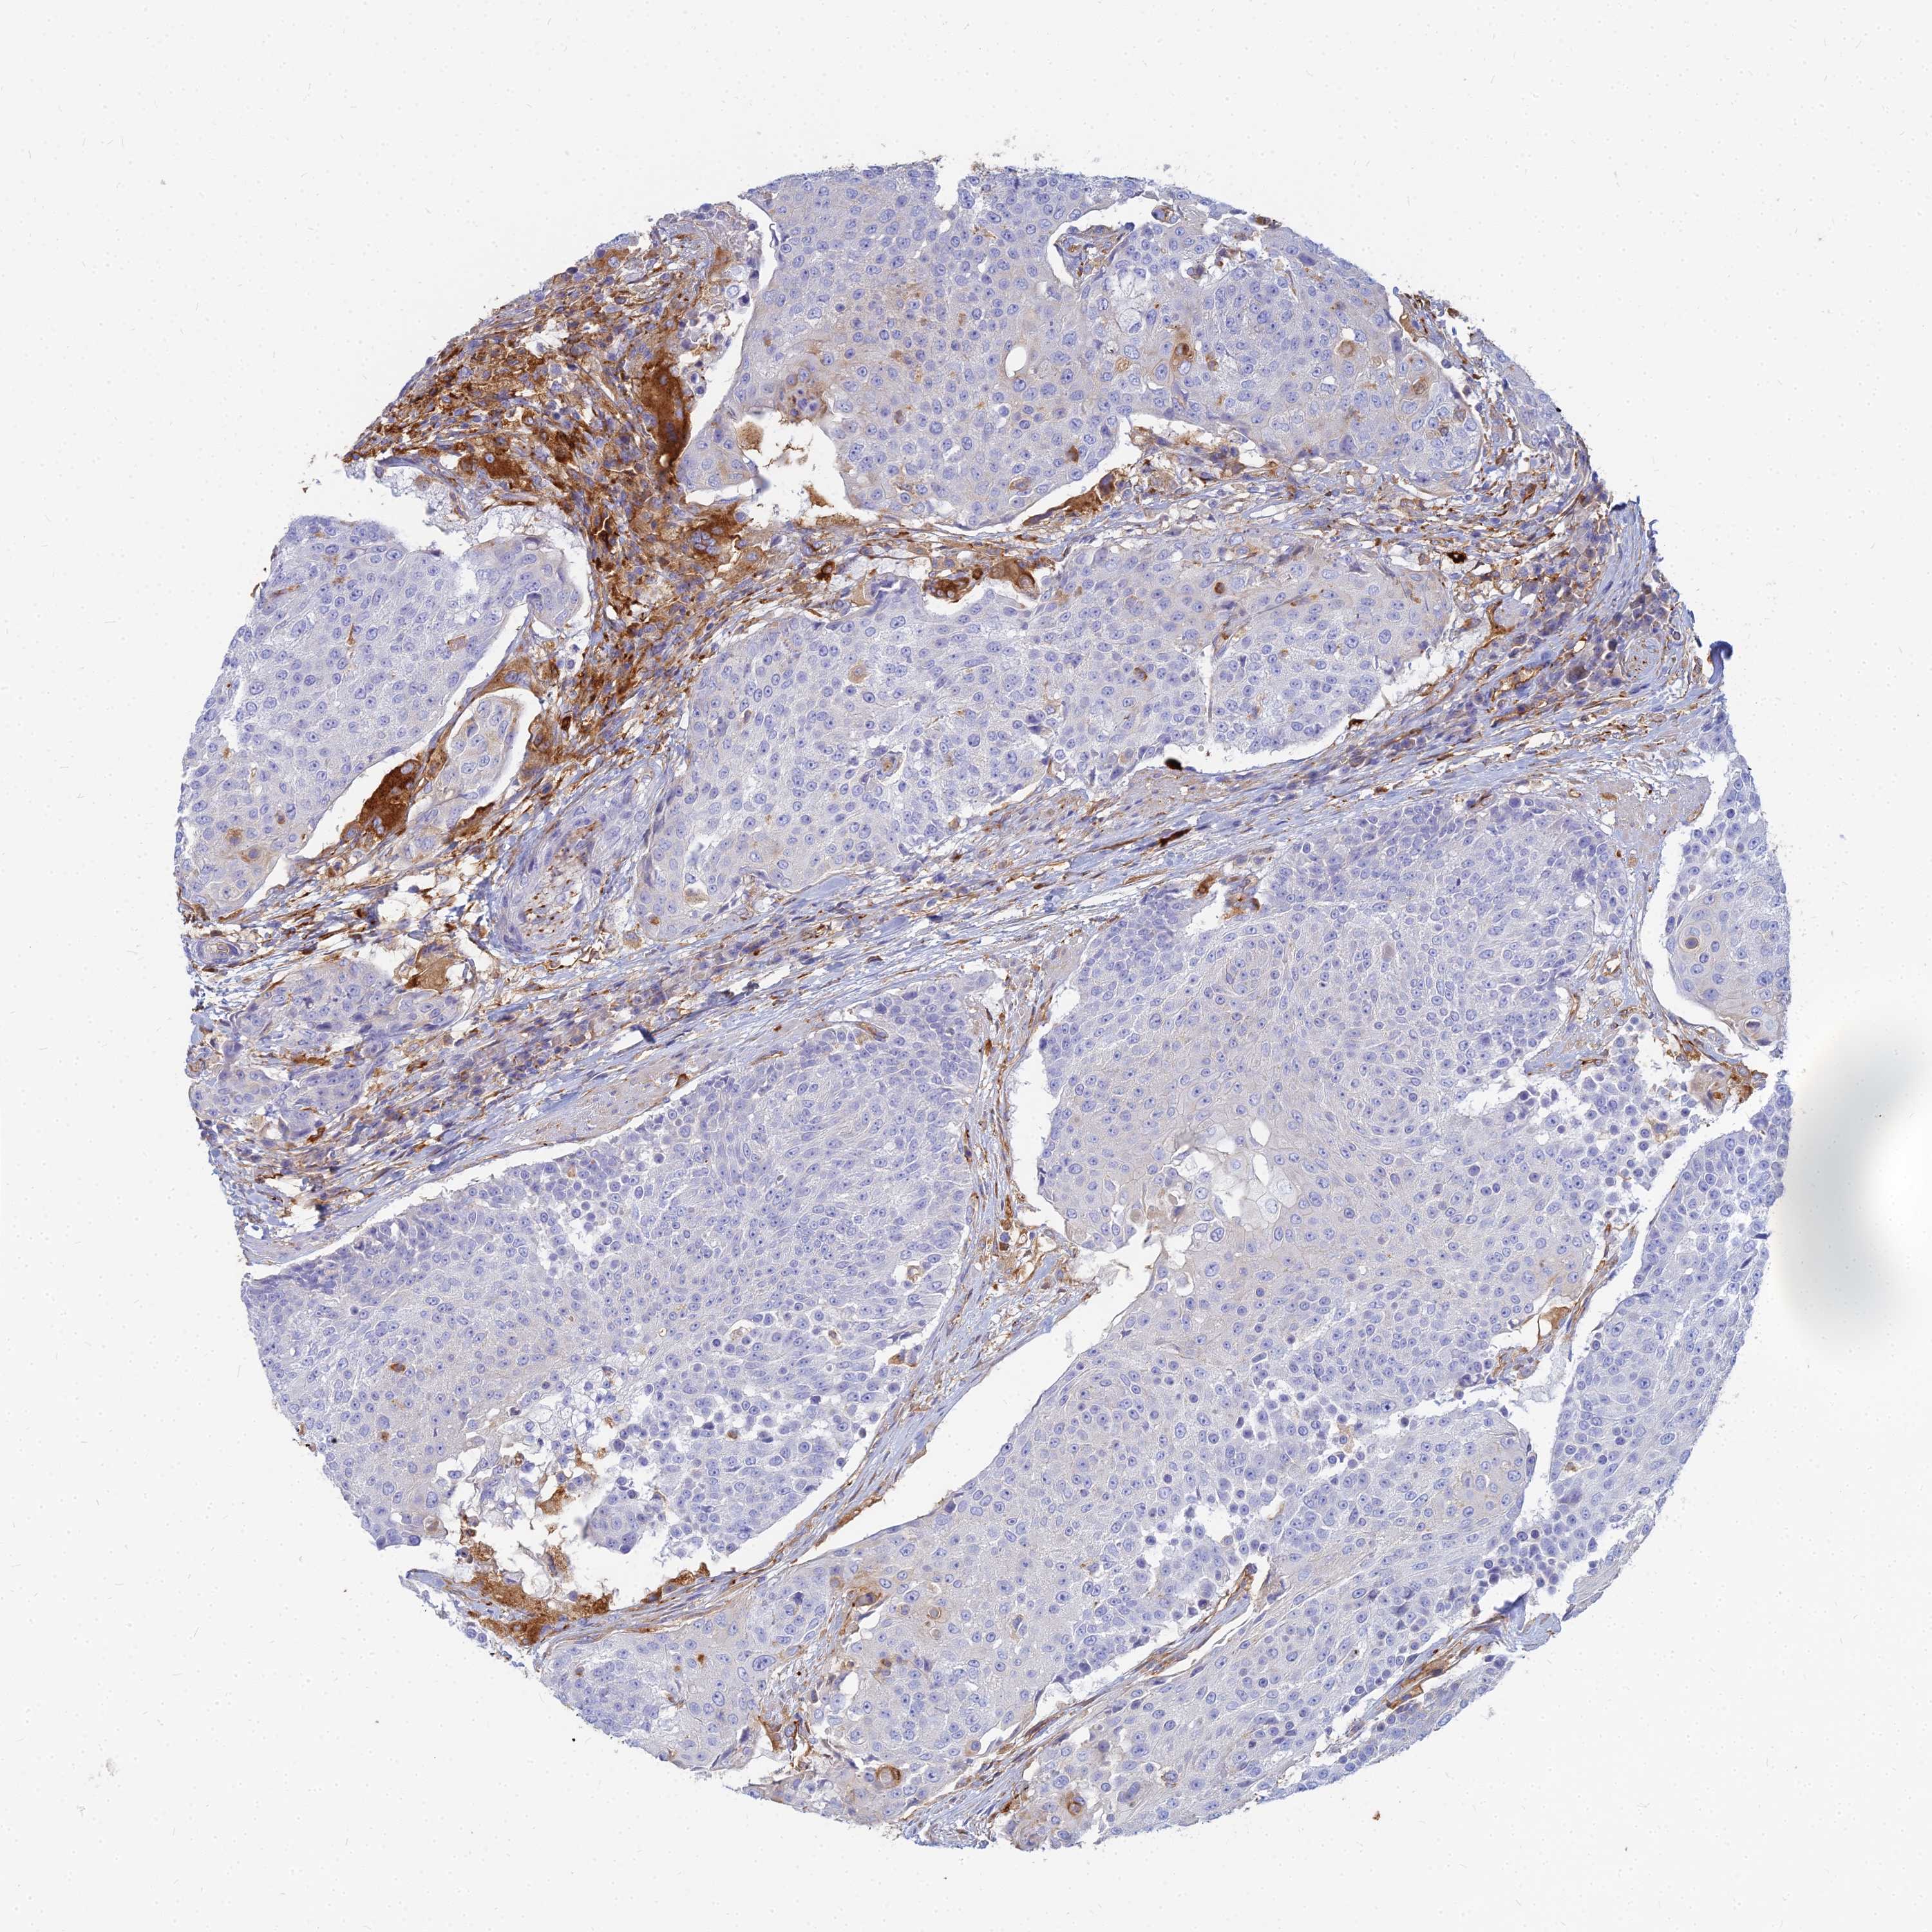

UROTHELIAL CANCER - Protein expressioni

A mouse-over function shows sample information and annotation data. Click on an image to view it in a full screen mode. Samples can be filtered based on level of antibody staining by selecting one or several of the following categories: high, medium, low and not detected. The assay and annotation is described here.

Note that samples used for immunohistochemistry by the Human Protein Atlas do not correspond to samples in the TCGA dataset.

Antibody stainingi

Antibody staining in the annotated cell types in the current human tissue is reported as not detected, low, medium, or high, based on conventional immunohistochemistry profiling in selected tissues. This score is based on the combination of the staining intensity and fraction of stained cells.

Each image is clickable and will lead to virtual microscopy that enables deeper exploration of all samples and also displays staining intensity scores, fraction scores and subcellular localization as well as patient and tissue information for each sample.

Antibody HPA045170

Staining

High

Medium

Low

Not detected

Intensity

Strong

Moderate

Weak

Negative

Quantity

>75%

75%-25%

<25%

None

Location

Nuclear

Cytoplasmic/membranous

Cytoplasmic/membranous,nuclear

Urothelial carcinoma, High grade

Urothelial carcinoma, Low grade